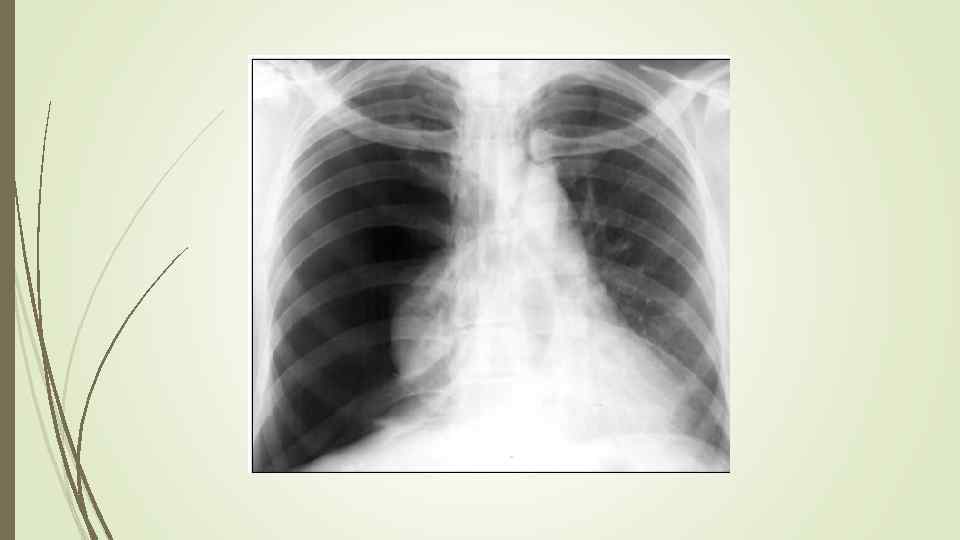

Бронхопневмония Характерно наличие двухсторонних множественных очаговых теней. Контуры очагов нечеткие, интенсивность тени небольшая. Инфильтрация неоднородна. Мелкие, малоинтенсивные очаги не всегда выявляются на снимках. Легочный рисунок усилен на всем протяжении легких. Корни расширены, не структурны. Как правило, отмечается реакция плевры, могут быть и экссудативные плевриты.

Бронхопневмония Характерно наличие двухсторонних множественных очаговых теней. Контуры очагов нечеткие, интенсивность тени небольшая. Инфильтрация неоднородна. Мелкие, малоинтенсивные очаги не всегда выявляются на снимках. Легочный рисунок усилен на всем протяжении легких. Корни расширены, не структурны. Как правило, отмечается реакция плевры, могут быть и экссудативные плевриты.